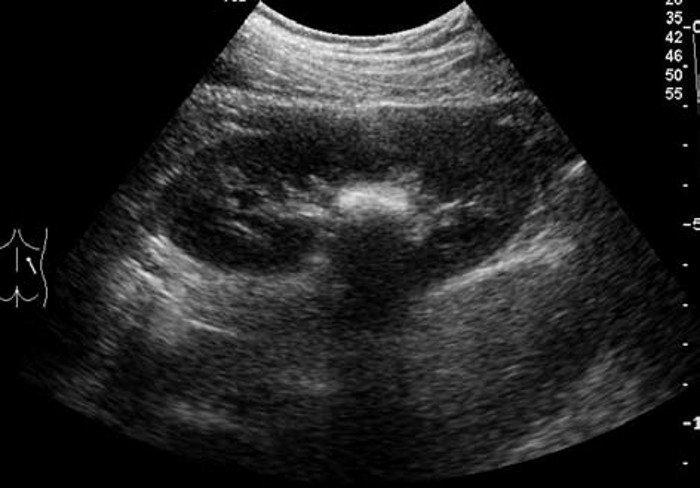

3. 鹿角状结石:大而分叉,形态不规则,超声往往仅显示局部突起的表面,呈几个孤立的强光团或弧形强回声带,像多个结石,但连续扫查可出现互相连续的一体。

患者,男,12岁,因运动后多次突发腹痛,腹痛不能缓解并伴有恶心,面色苍白来院就诊,尿常规检查可见红细胞。超声检查显示:双肾大小形态大致正常,轮廓清,包膜光滑,实质回声尚均,呈低回声。右肾未见明显分离,左肾集合系统分离约1.1cm,左肾内可见0.9cm×0.7cm强回声,后方有声影。

超声提示:左肾集合系统分离,左肾结石。